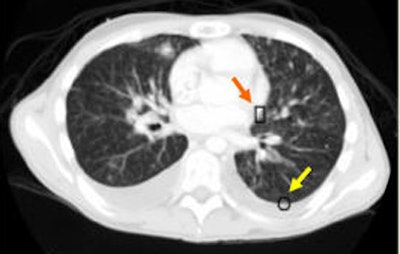

![]() |

| An example of successful nodule classification. The circle encloses a true wall nodule. The rectangle surrounds a very similar wall object that is in fact a false positive erroneously detected by the group's previous CAD system. The current hybrid FP reduction approach recognizes and removes this false-positive finding. |